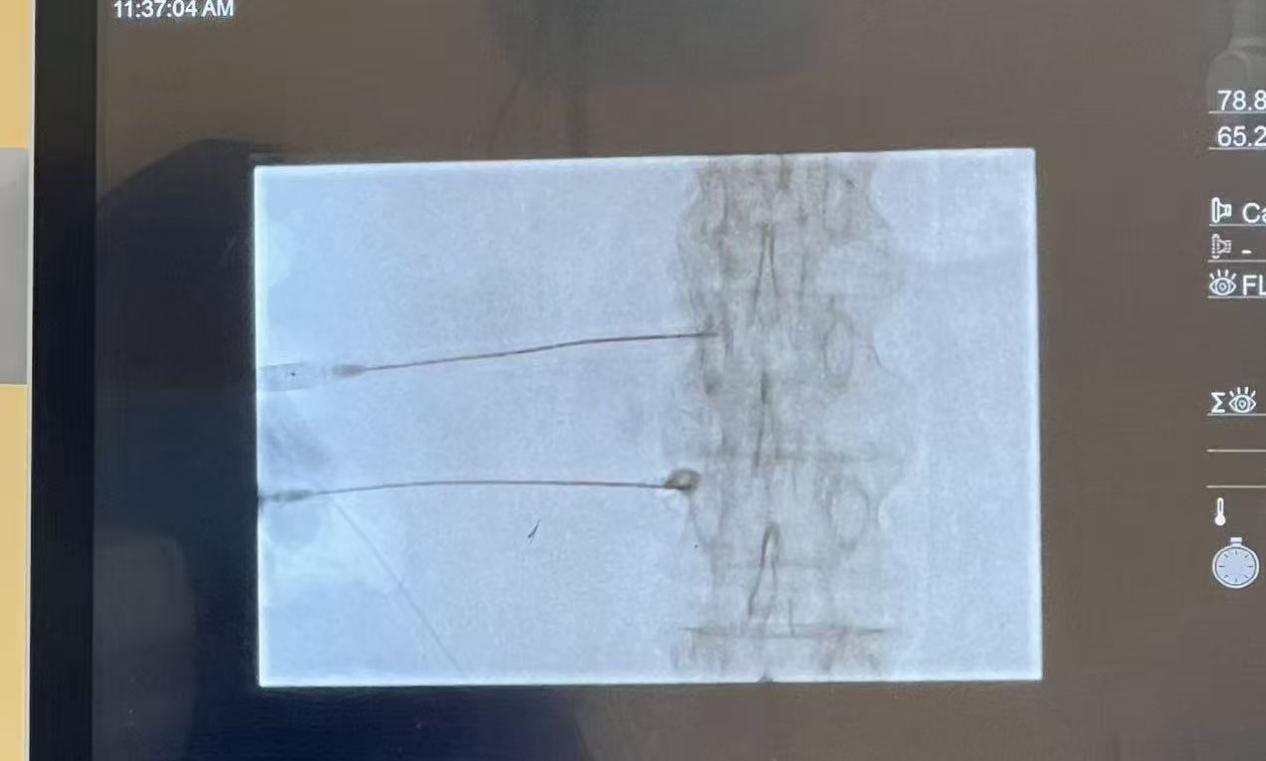

这个治疗全程在局麻下进行,医生会用一根很细的射频针,在CT引导下找到腰交感神经节的位置。通过射频能量温和地调节神经功能,就像给失灵的“开关”做了一次“校准”,让它恢复正常的调节能力,不再过度收缩血管。术后当天就能下床,伤口只有针眼大小,基本不用拆线。